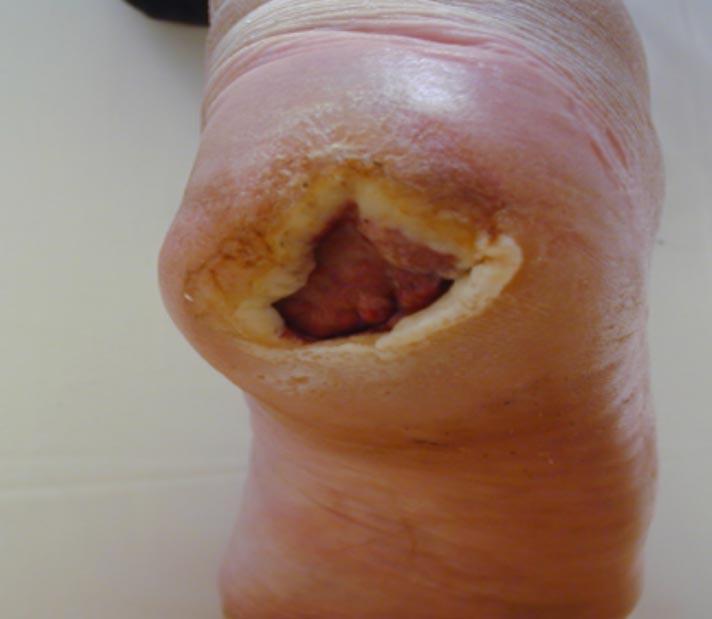

Zahájení léčby a stav po 22 převazech

Zahájení léčby a stav po 22 převazech.